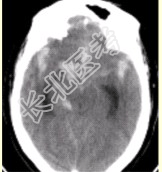

- [材料题] 患者男,50岁,突发昏迷、呕吐1h。查体:颈项强直,脑膜刺激征阳性,CT表现如图1。

- 单项选择题1.初步诊断应为

A、脑血肿

B、脑梗死

C、蛛网膜下腔出血

D、脑血管动静脉畸形

E、正常